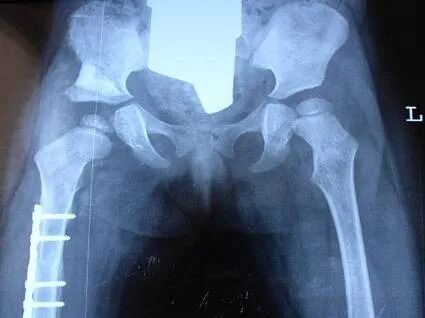

会诊手术! 马蹄内翻足 发育性髋关节脱位 学科带头人介绍 卢成 骨科主任 从事骨科临床工作二十多年,曾于2011年在清华大学附属医院师从中国著名矫形外科专家秦泗河教授学习矫形外科,积累了大量的临床诊疗经验。熟悉骨科常见病、多发病的诊断及治疗,在四肢畸形矫正及骨外固定技术领域有较深的造诣。 擅长:骨外固定及Iizarov技术治疗各种下肢畸形包括脊髓灰质炎后遗症、脑瘫肢体功能障碍、先天性髋关节脱位、膝内、外翻、先天性多发性关节挛缩症、骨缺损、骨不连、骨髓炎,以及先天性马蹄内翻足、拇外翻等各种复杂的足踝部畸形、脊柱裂后遗各种下肢畸形等。同时在成骨性肿瘤、成软骨性肿瘤、骨肉瘤等骨肿瘤疾病的治疗,股骨头坏死、颈椎病/腰椎病的手术治疗、椎体成形术、关节创伤、关节置换等方面也有颇深的造诣。 欢迎安徽省及周边地区患友积极就诊、复查。凡在